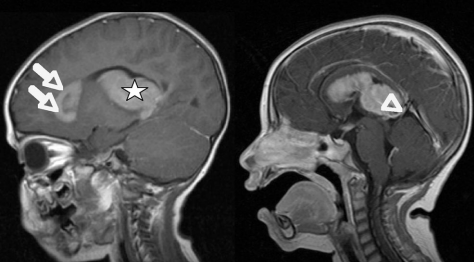

图 2 术前矢状位对比增强 T1 加权磁共振成像。病变的分布清晰可见。右侧可见病变与大脑内静脉的紧密联系(箭头所指)。箭头标记了沿脑室额角分布的病变。星号表示轴内主要病变。